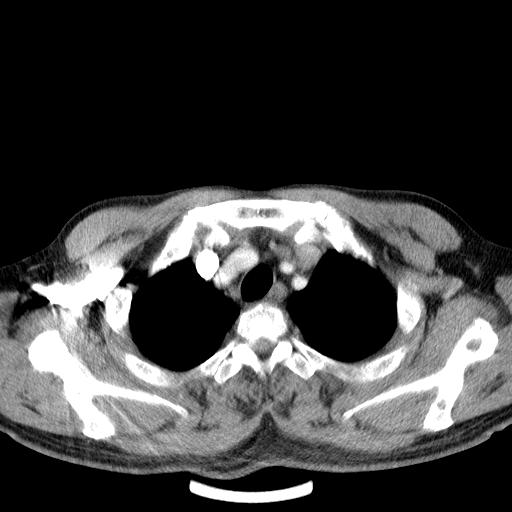

先行ct平扫,纵膈内多发软组织影,ct值约为36hu,以下为增强扫描和腹部平扫。

请会诊